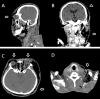

Necrotizing fasciitis (NF) is uncommon but potentially lethal when it is associated with systemic disorders. We report a case of odontogenic NF in a patient with uncontrolled diabetes mellitus. The patient was referred on day 10 since the onset of odontogenic NF. Protective tracheostomy, local facial-cervical fasciotomy were conducted and broadspectrum antibiotics were given, subsequent serial surgical drainage and debridement were performed in theater. Staphylococcus aureus, Pseudomonas aeruginosa, and Klebsiella pneumonia were isolated. Five staged debridements were performed to the targeted anatomic regions thus reducing surgical time and blood loss. The patient survived the acute infection and received subsequent reconstruction. Cervical NF with descending mediastinitis and periorbital NF is associated with high mortality rates. This is the only known report of an adult who survived NF affecting entire scalp, periorbital, cervical, and thoracic region. Early diagnosis and staged surgical planning minimize morbidity and mortality from NF.